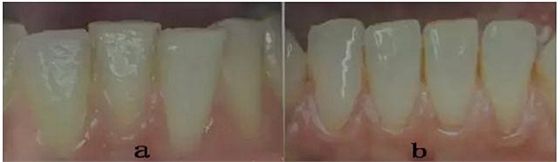

2.減少或改善牙齦間隙(黑三角)牙冠呈三角形比呈矩形的牙齒更適合IPR(圖1a,b)